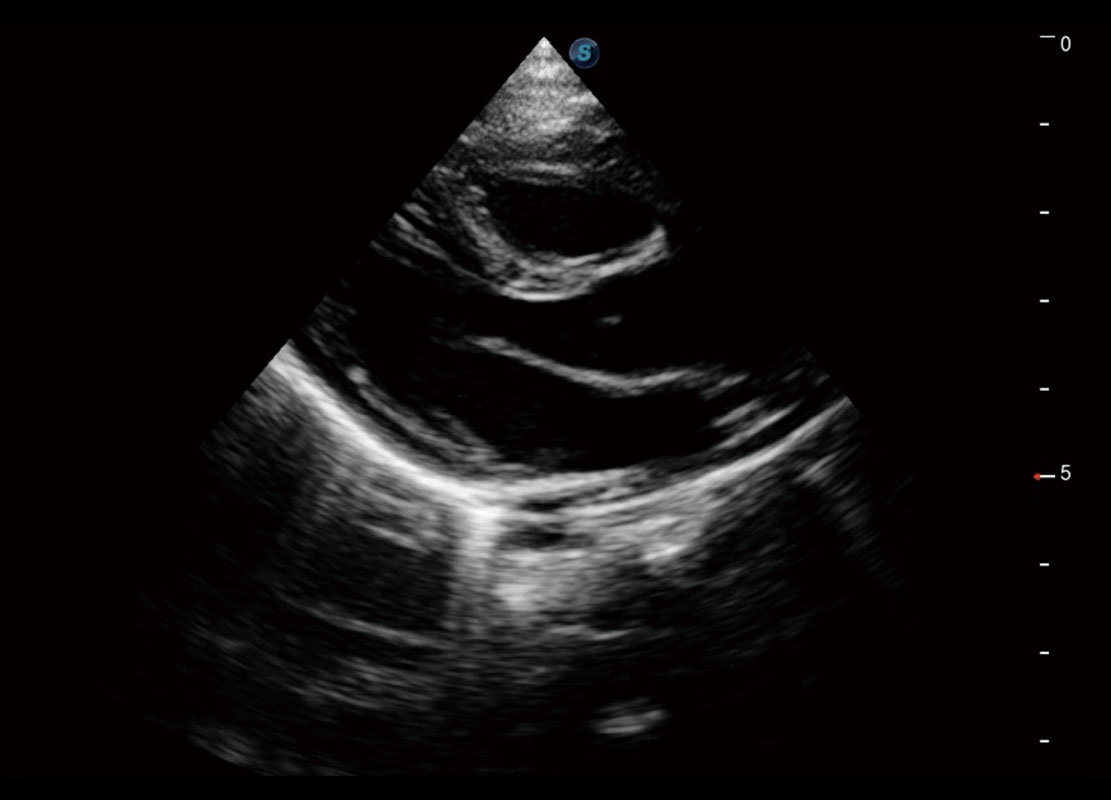

• 新生儿心脏